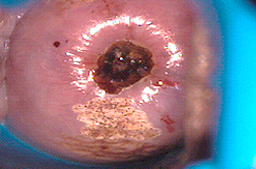

Cuando se utiliza en vagina, vulva y pene puede dar una profundidad mayor de la deseada y ocasionar problemas de cicatrización como se observa en las imágenes, o perforaciones del tejido hacia vejiga y/o recto.